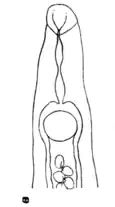

| Fig. 130.—Schistosomum hæmatobium; anterior end of male. (After Looss.) |

Fig. 131.—Schistosomum hæmatobium. Diagram of transverse section of male and female. |

Etiology.—Schistosomum hæmatobium (Figs. 129, 130, 131) is a bisexual trematode belonging to the family Schistosomidæ. The male is white, cylindroid, 11 to 15 mm. in length by 1 mm. in breadth. It possesses an oral and a ventral sucker of about equal size and placed close together. The cylindrical appearance of the worm is produced by the ventral infolding of the two sides of what would otherwise be a flat body. By this infolding a gynæcophoric canal is formed, in which the female can be partially enclosed. The outer surface of the body is closely beset with small cuticular prominences. The female is rather darker in colour than the male, considerably longer (20 mm.), more filiform, her middle being usually enclosed in the gynæcophoric canal referred to, whilst her anterior and posterior portions remain free. The genital openings of the sexes face each other, and are placed immediately posterior to the ventral sucker. The sexes live apart while young, but on reaching maturity the female enters the gynæcophoric canal of the male.